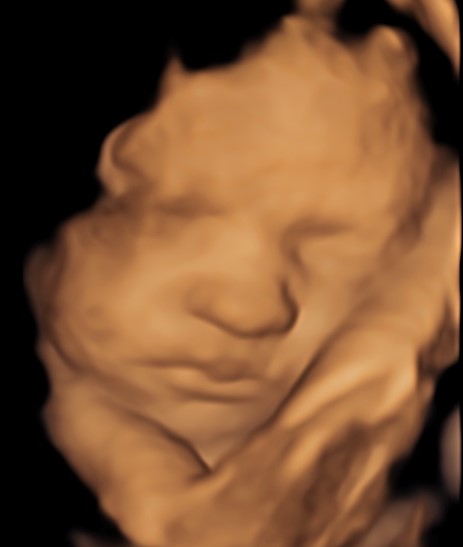

4D/5D/HD Ultrasound Gallery

Gallery